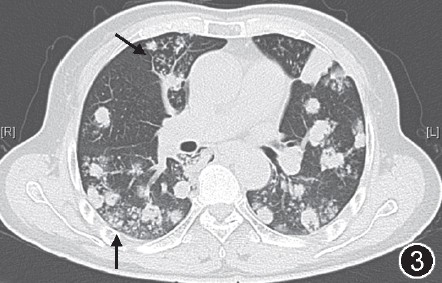

【答案公布】双肺多发结节及肿块影

【三甲读片】两肺多发结节,激素治疗后消失,你